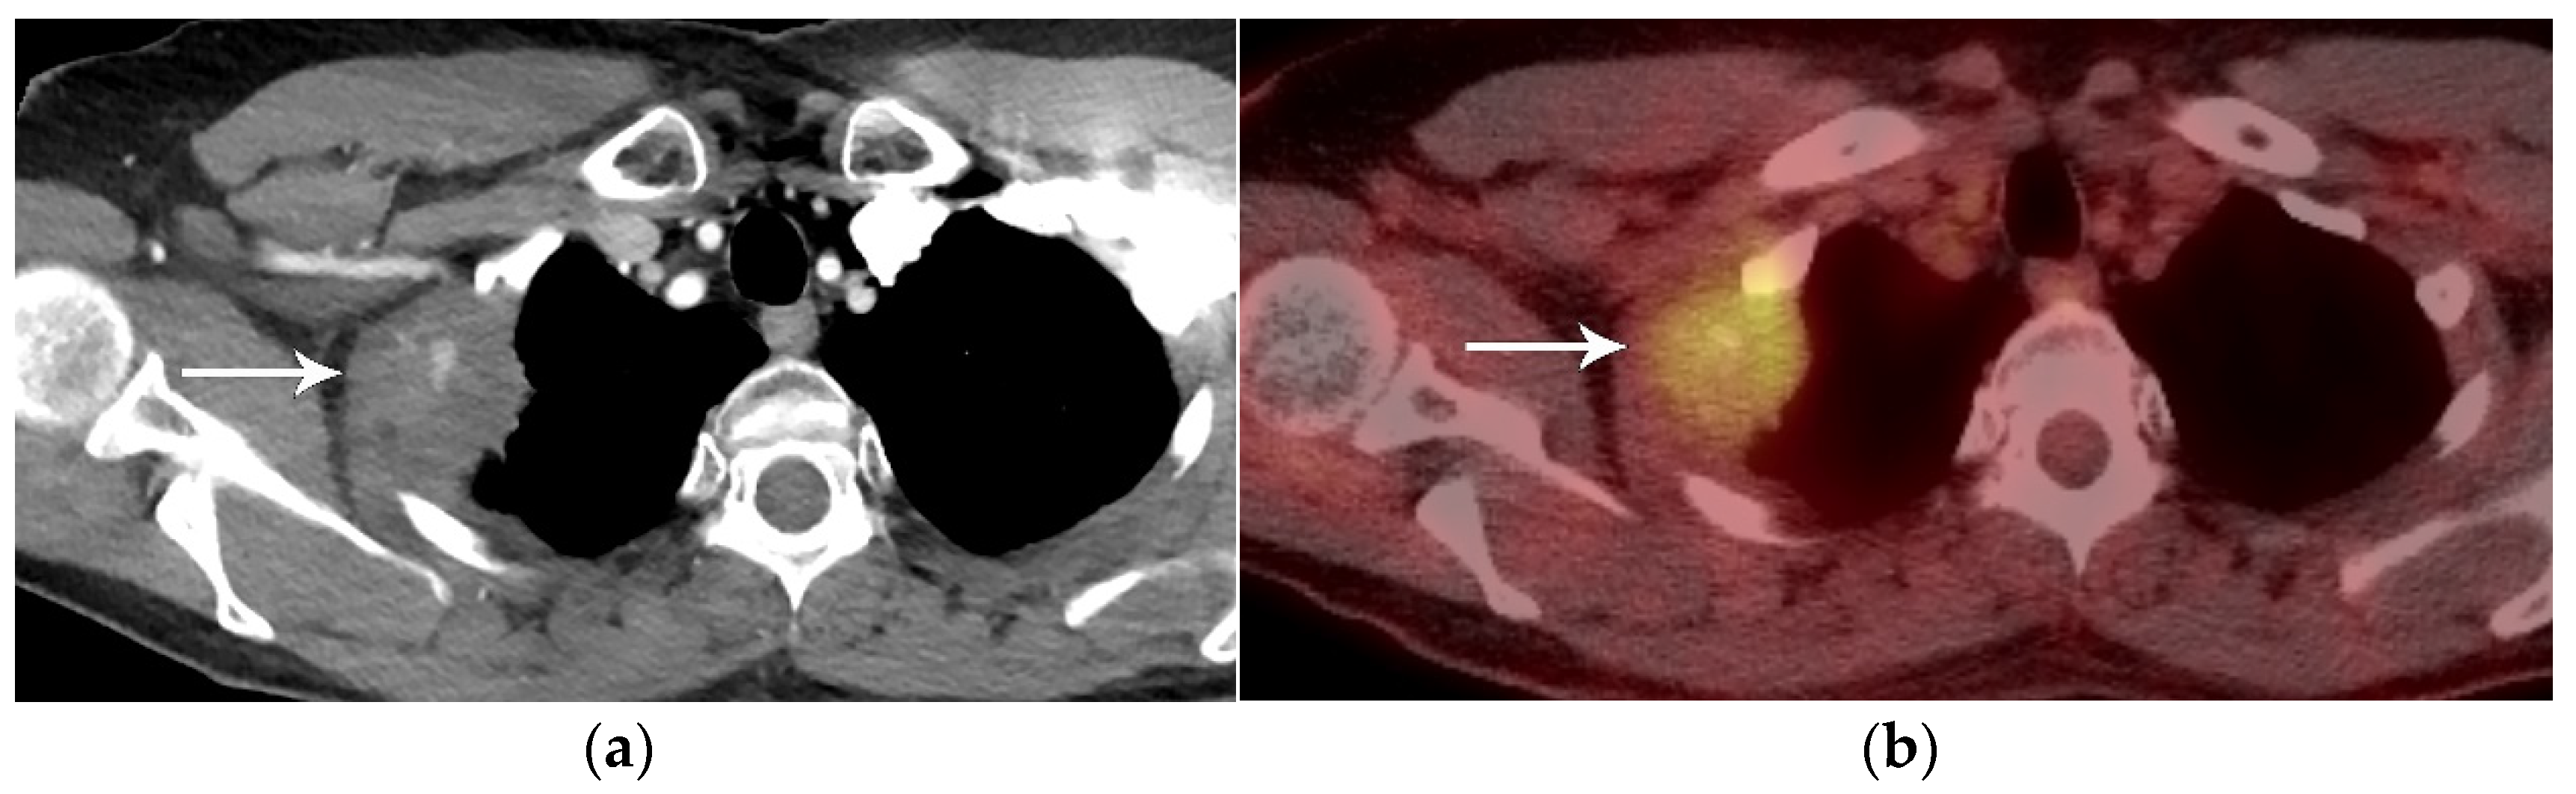

3. N Classification

4. M Classification